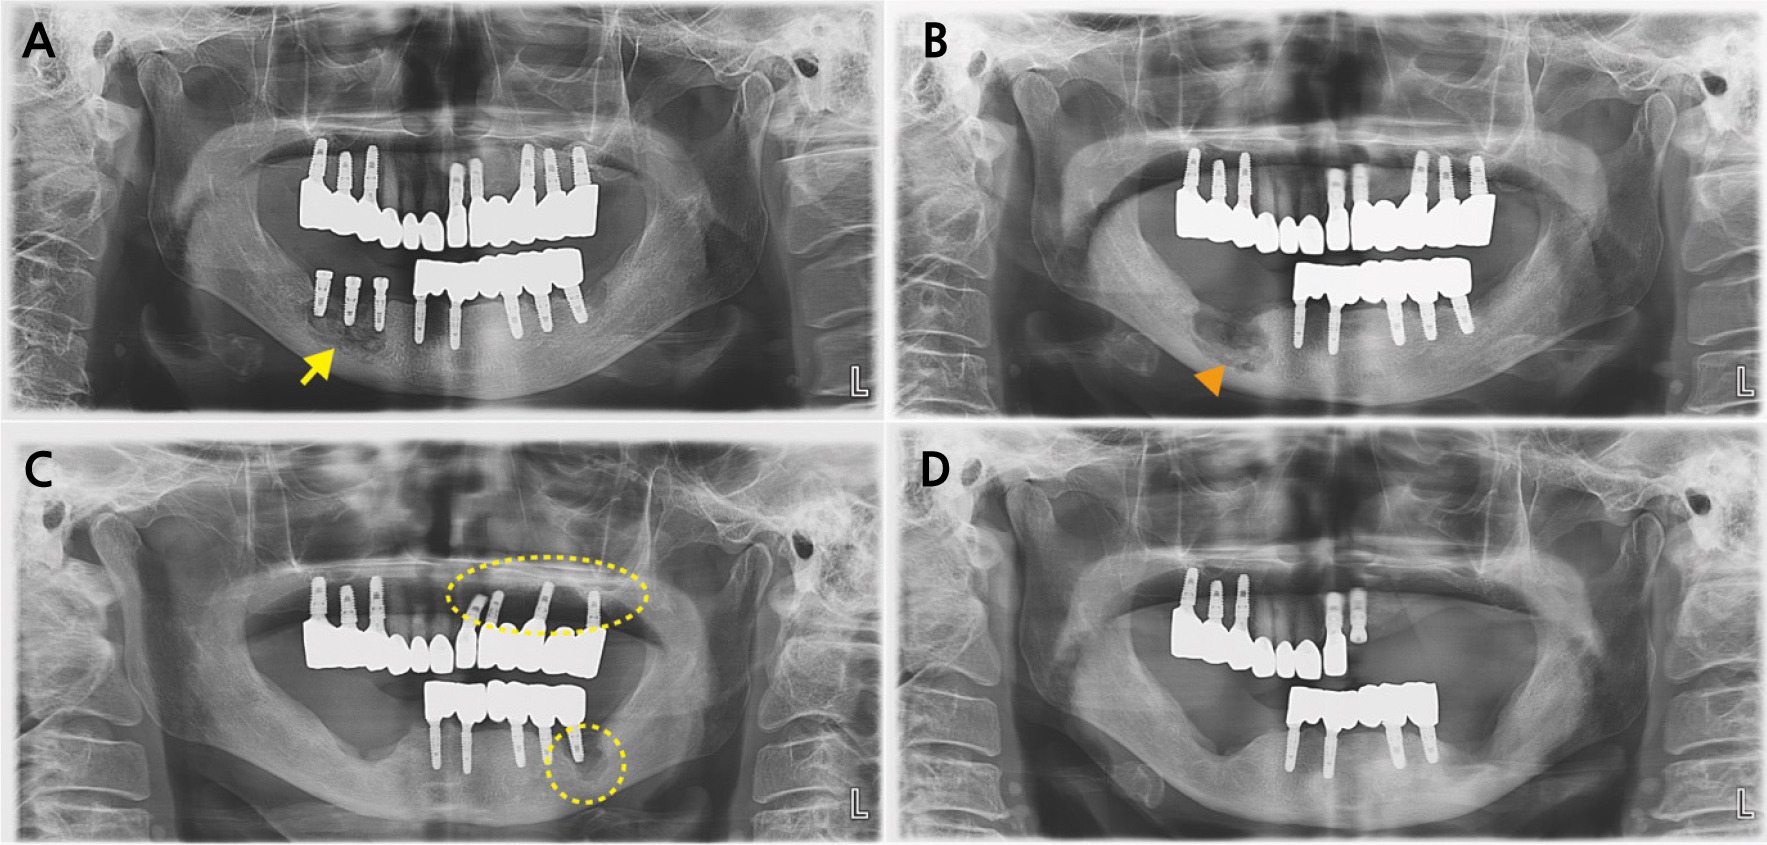

A panoramic radiograph obtained at the initial visit revealed sequestrum formation around implants #44, #45, and #46 (Fig. 3A). The patient subsequently underwent sequestrectomy and implant removal. During follow-up, additional sequestrum formation was observed, thereby necessitating a second surgical intervention (Fig. 3B).

Regarding osteoporosis management, the patient received Forsteo (teriparatide, subcutaneous injection) in March and April 2021, followed by Evenity (romosozumab, subcutaneous injection once monthly) for a total of 11 doses between May 2021 and August 2022, with a treatment interruption from May to October 2021. A single Prolia (denosumab, 60 mg subcutaneous injection) dose was administered on September 27, 2022, following completion of Evenity therapy. Subsequently, she was prescribed DicaMAX D (calcium carbonate and cholecalciferol concentrate; Darim Biotech Co., Ltd.) and resumed Forsteo (teriparatide, subcutaneous injection) from January 2024 to December 2024. After sequestrectomy, the right mandibular bone demonstrated satisfactory healing. However, new lesions later developed around the implants in the left maxilla and mandible, extending beyond the alveolar bone (Stage 3), which required additional surgical management (Fig. 3C and 3D). The two cases are summarized chronologically below (Table 1).

Fig. 3

(A) Panoramic radiograph at the first visit (Case 2) showing sequestrum formation around the implants on #44–#46 (yellow arrow), (B) Additional sequestrum formation was observed during follow-up (orange arrowhead), (C) After sequestrectomy, the right mandible demonstrated satisfactory healing; however, new lesions developed around the implants in the left maxilla and mandible (yellow dotted line), (D) The patient showed a favorable prognosis following additional surgery.